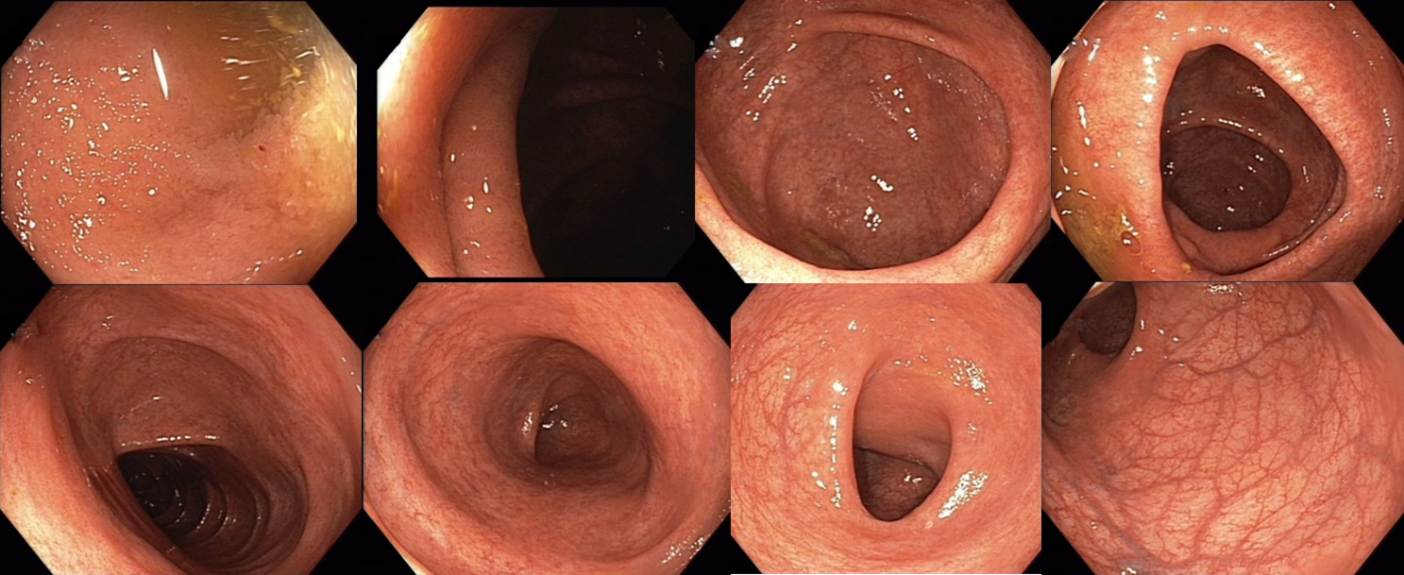

018/2 Slizniční zhojení. Monoterapie vedolizumabem

Slizniční zhojení

Histologie: lehká porucha architektoniky krypt, může se jednat o pozánětlivé změny. Jiné histopatologické změny přítomny nejsou.